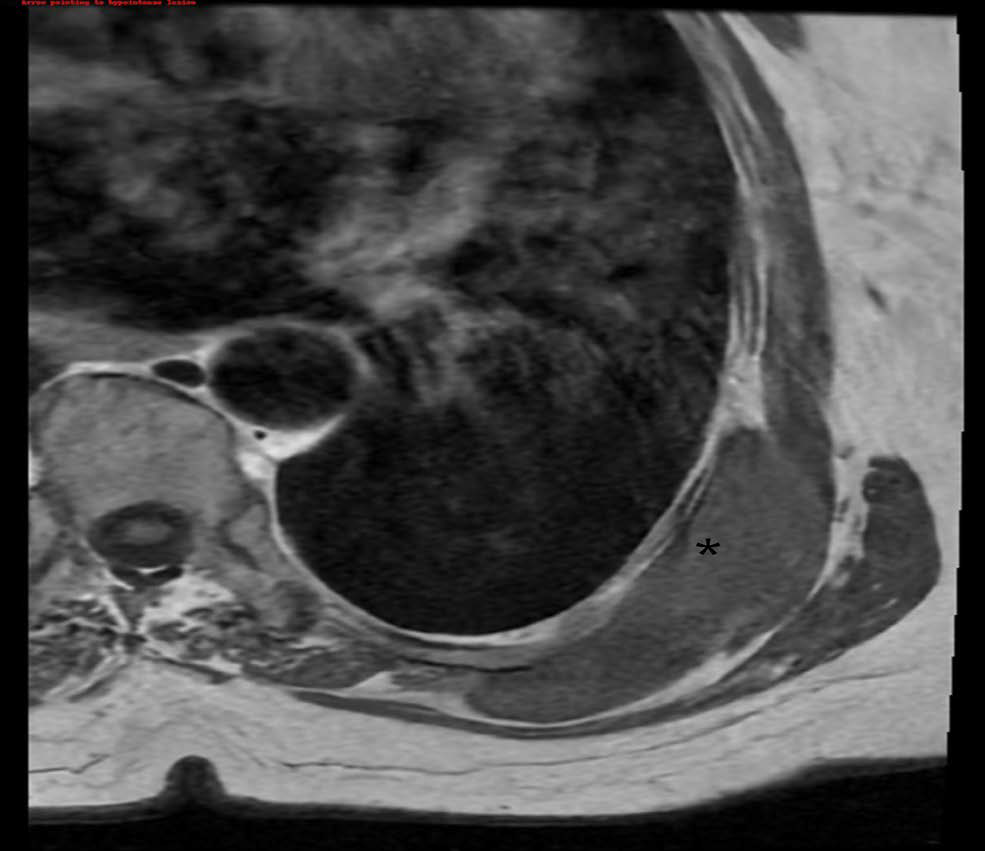

Early CT Diagnosis of Strangulated Obturator Hernia in a 93-Year-Old Woman Followed by Laparoscopic TAPP Repair: Case Report

Minh Duc Pham, Thanh Xuan Nguyen, Duc Anh Le, Duc Phu Tran, Huu Son Nguyen

1-8